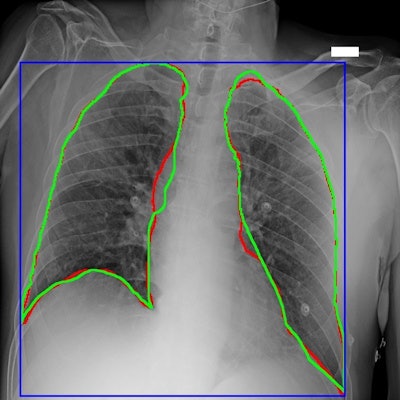

Bracco Imaging and partners in Italy have released a large dataset of chest x-rays from COVID-19 patients to facilitate the development of artificial intelligence (AI) algorithms.

Available with open access to the global scientific community, the AIforCOVID Imaging Archive contains more than 1,000 chest radiographs from COVID-19 patients along with clinical information about the patient. The data was collected as part of the nonprofit AIforCOVID initiative, which was promoted by Bracco in partnership with the Italian Diagnostic Center, according to the vendor.